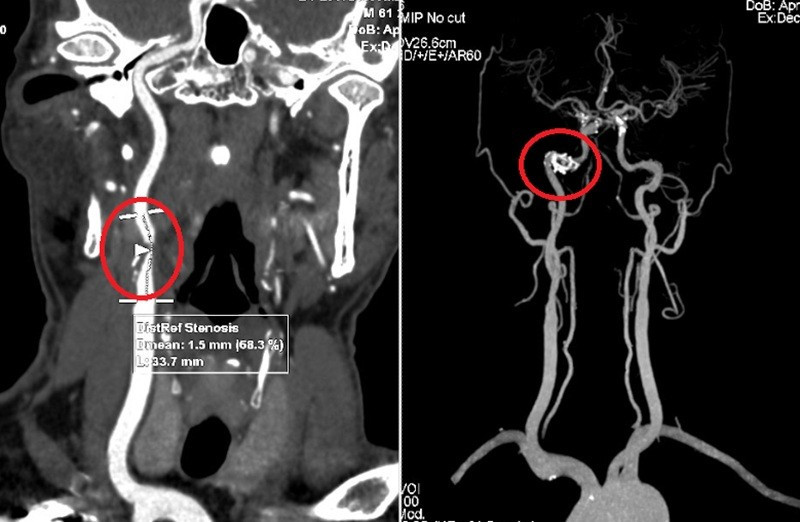

Chụp cắt lớp vi tính phát hiện mảng xơ vữa gây hẹp nặng động mạch cảnh trong bên phải. Ảnh Medlatec

Kết quả chụp cắt lớp vi tính động mạch cảnh tiếp tục khẳng định hình ảnh mảng xơ vữa hỗn hợp tại động mạch cảnh trong bên phải, gây hẹp 68% lòng mạch. Chụp MRI sọ não cho thấy còn tồn tại một số ổ nhồi máu não cũ và mới ở vùng thái dương - đỉnh phải.